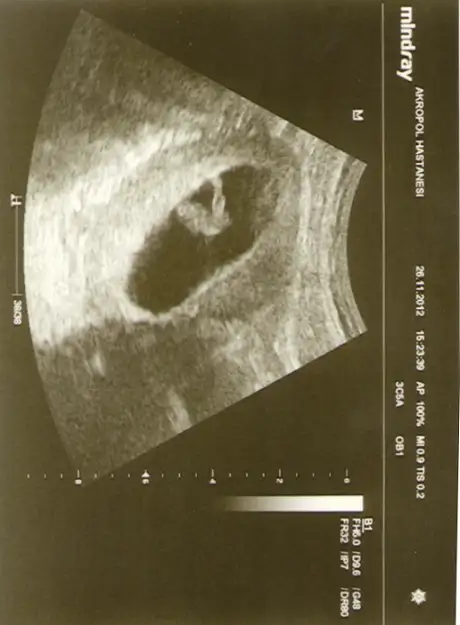

merhabaaa arkadaşlaarr... bebeğimin 8+0 haftalıkken olan görüntüsü... yan koymamın sebebi bebeğin yatış pozisyonunda rahat görebilmeniz için... ben nub teorisine göre bi cinsiyet tahmininde bulundum ama sizlerinde fikrini almak istiyorum.. nub görüntüsü belli olduğu için bu haftada koydum... sağ tarafta dikkatlice bakınca görebilirsiniz sanırım...

Ggobek kordonun altinda erkek olabilir tabi henuz erken

ultrason görüntülerinde cinsiyeti erkek olunca erkenden yani 3,5 aylıkken belli oluyor. ama cinsdiyeti 5.aya kadar belli olmayınca büyük olasılıkla cinsiyeti kız oluyor.

ingilizce bilenler www.in-gender.com adresine ejklesin resimleri orda teknisyenler bakip soyluyor:) tokayay sadece seninkisi kizdan erkege donebilcek bir nub. kacinci haftada baktirdin? 13.hafta icinde en kesin sonuc veriyorlar, erkek nublari 12.hafda sonunda oldukca aci vermis oluyor. onceden bakilabilenler degisebilir, ozelikle kiz denenler erkek cikabilir. ama yukardaki ilk iki arkadasinki cok klasik kiz nubu. Allah herkesin gonlundekini nasip etsin. bizim yorumlarimizi da aslinda cok ciddiye almamak lazim. ama bu ing sitesinde yuzde 95 biliyorlar desem:))